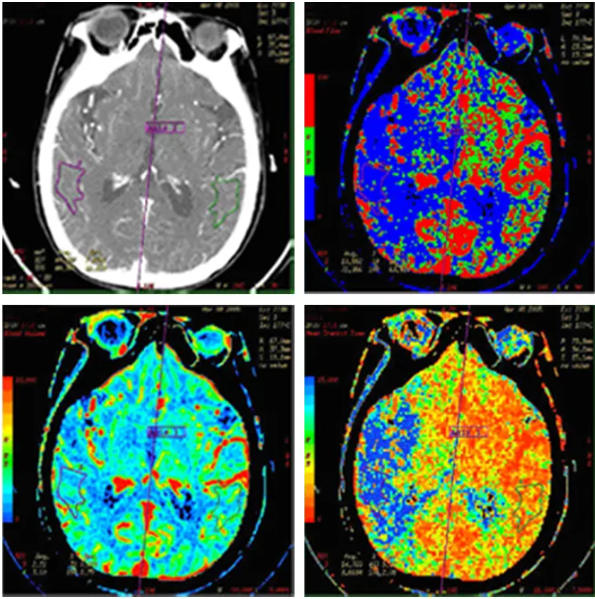

新设备的引进让我们又多了一项新技术--“CT脑灌注成像”。CT脑灌注成像是对选定层面进行连续动态扫描,获得所选层面的每一像素的时间密度曲线,并通过数学模型处理得到脑血容量、脑血流量、对比剂平均通过时间、对比剂达峰值时间等血流动力学参数和灌注图像表现,能有效评价脑组织的灌注状态,能更有效并量化反应局部脑组织血流灌注的改变,是一种CT应用领域的前沿科技,对明确病灶的血液供应具有重要意义。

它可以早于核磁共振弥散加权像(DWI)发现脑梗死,可以发现DWI不能发现的脑梗死前期脑组织局部缺血区及生理学改变,明确区分缺血半暗带,有利于溶栓和预后的判断,也是目前公认的对缺血半暗带能做出的最科学的评估方法。